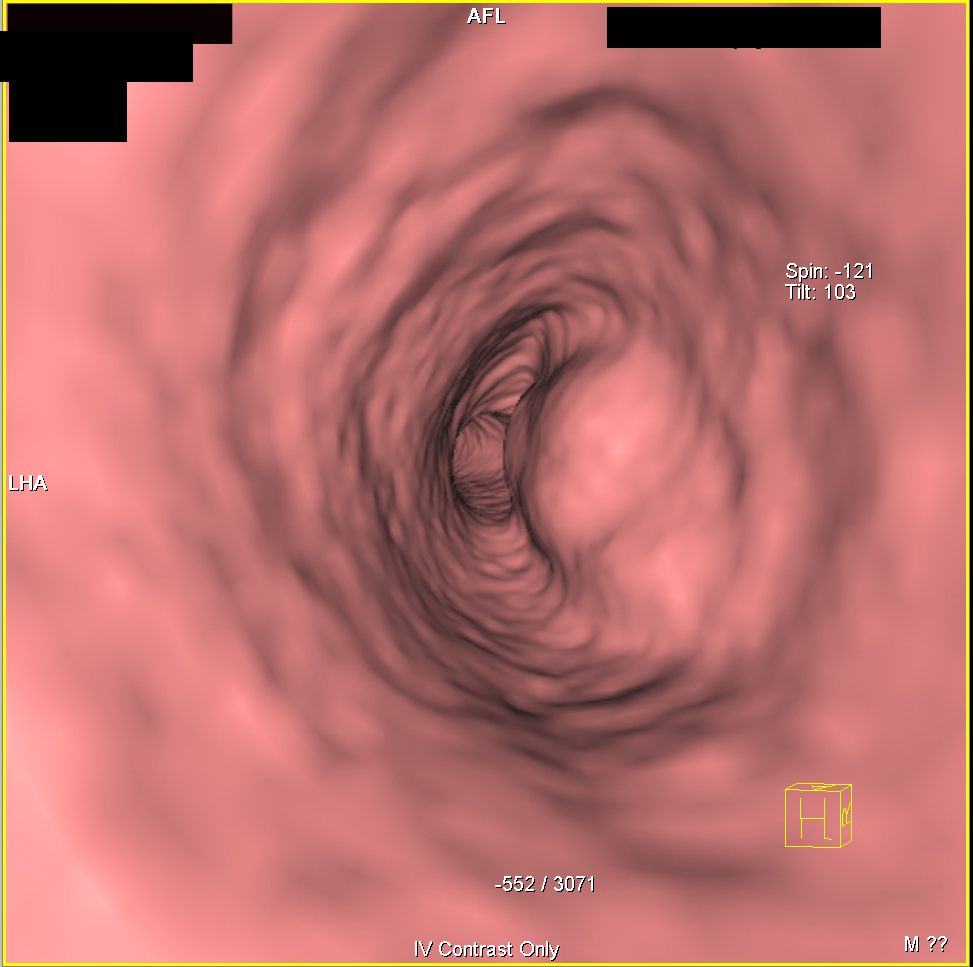

5) In this patient with cough the most likely dx is?

amyloidosis

metastatic tumor to trachea

adenoid cystic carcinoma

duplication cyst